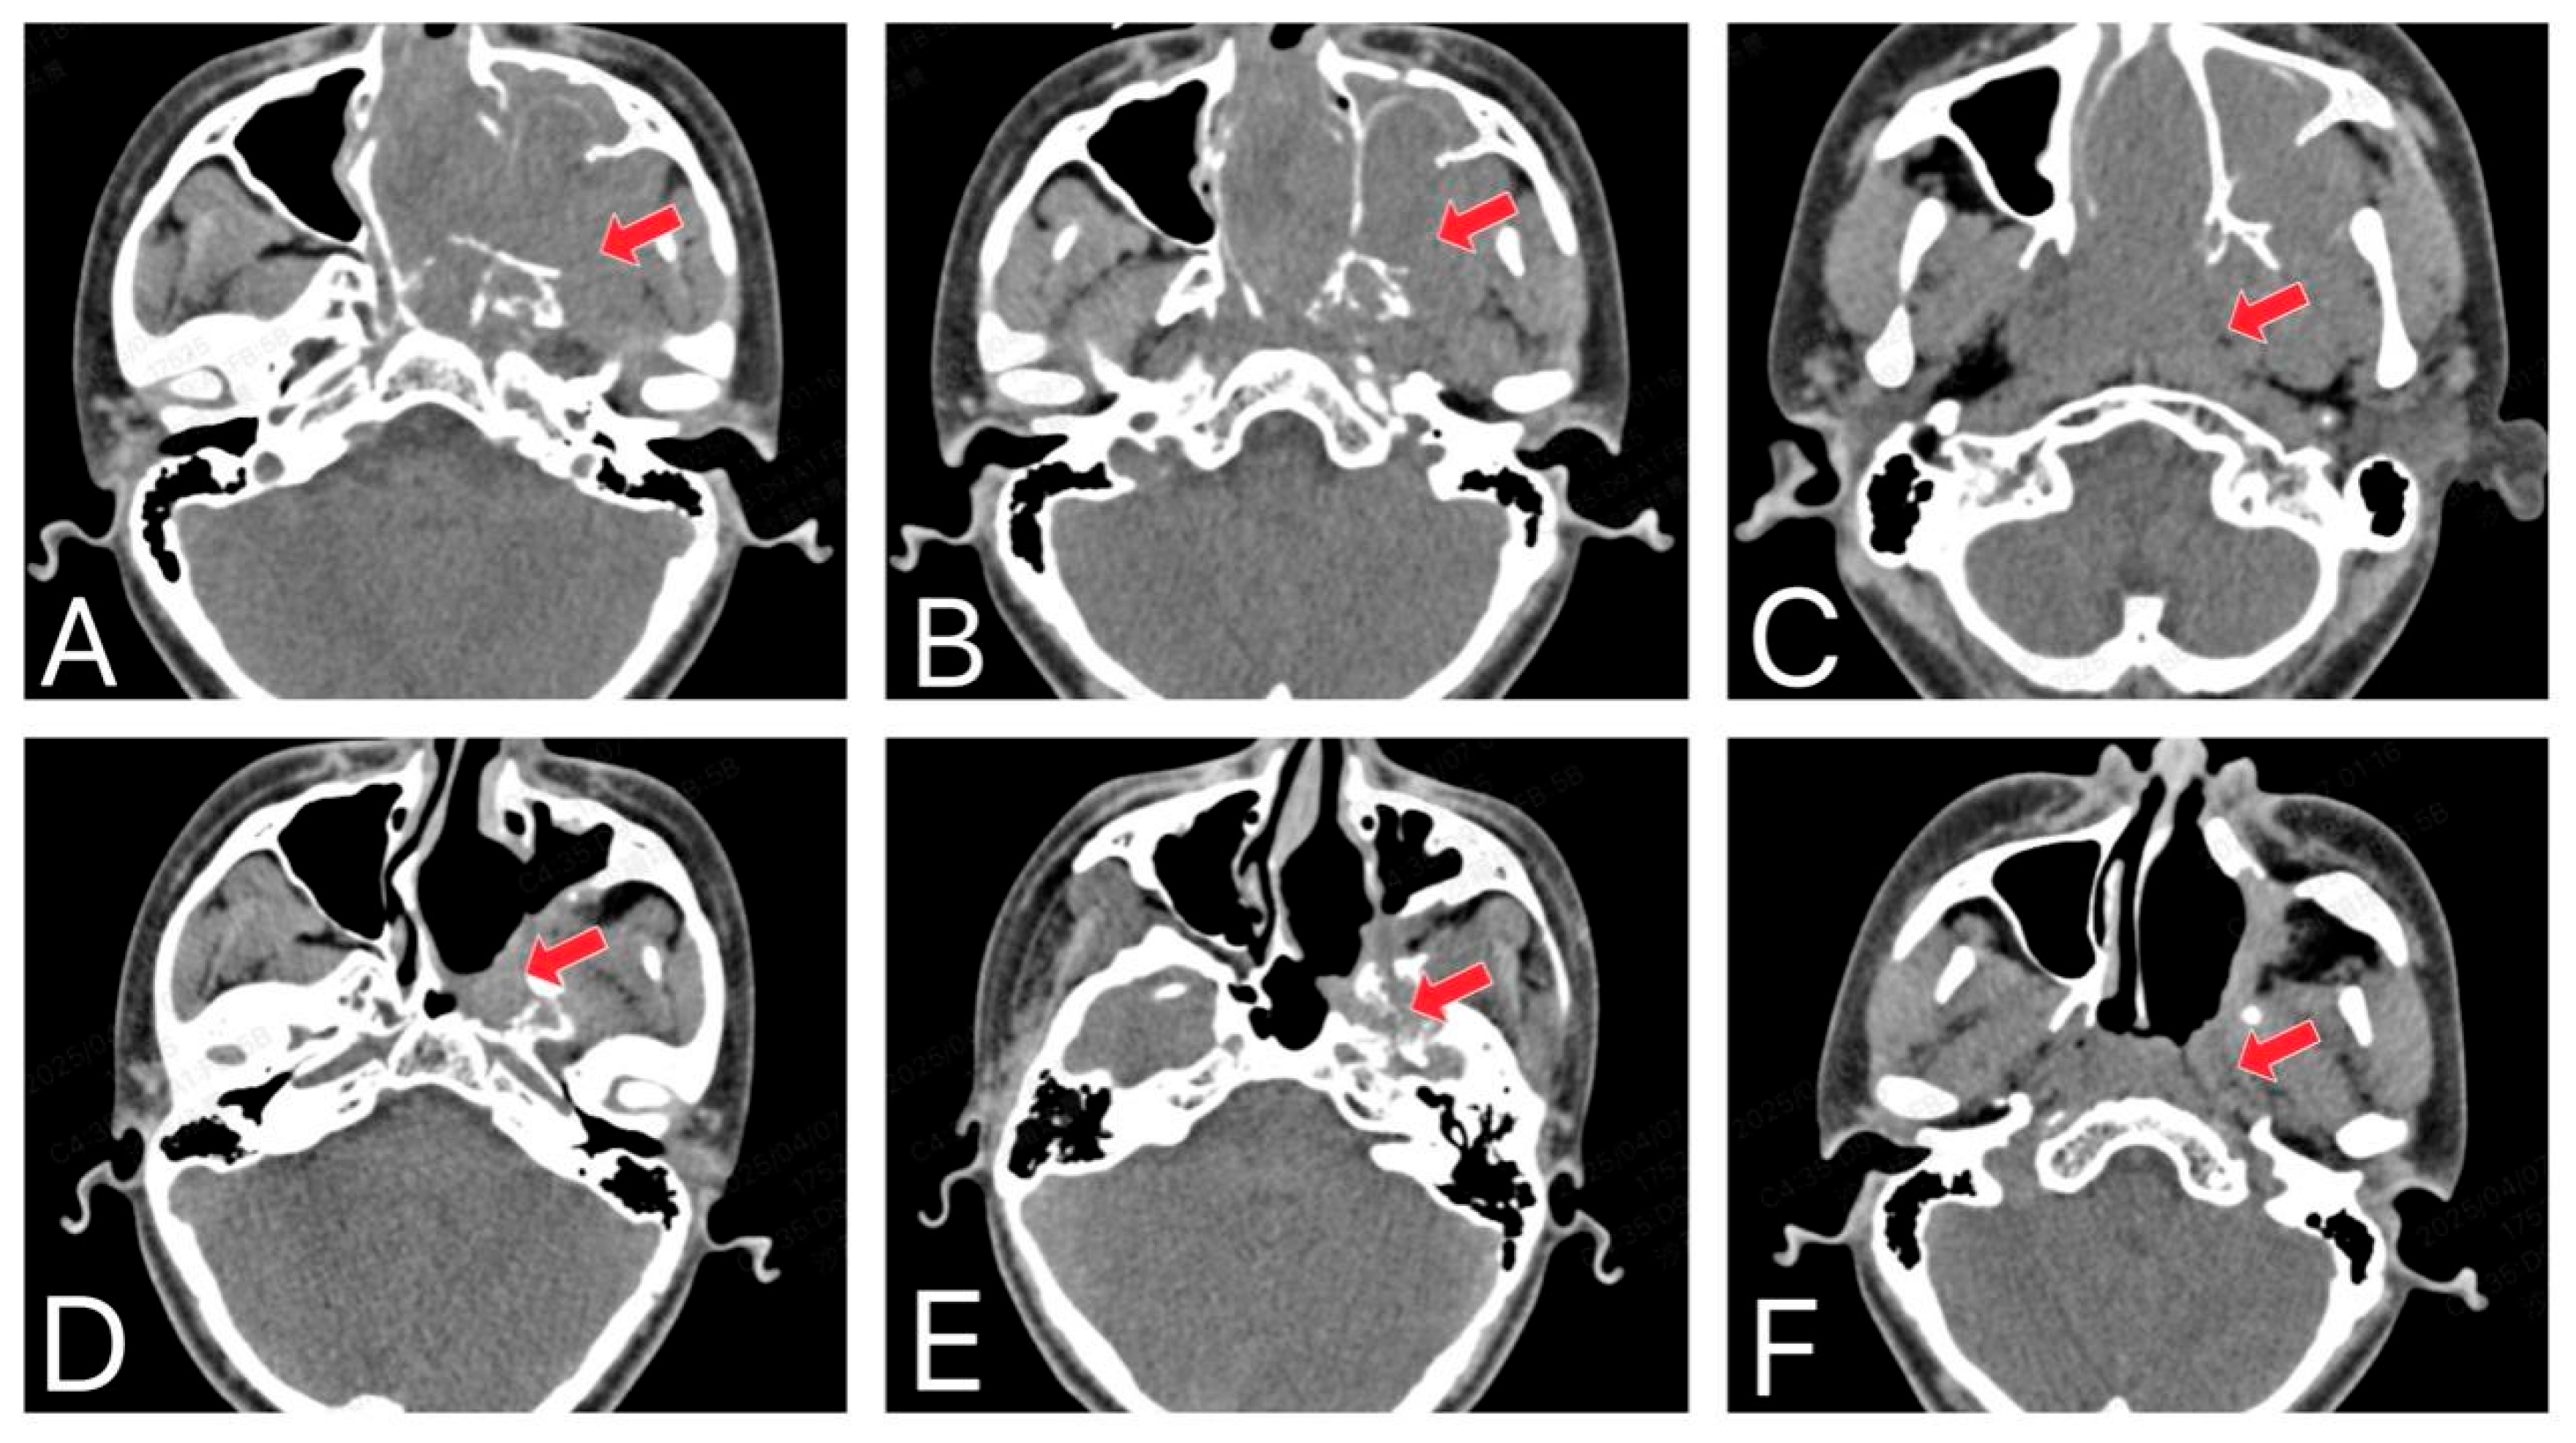

Figure 2.

The invasive nature and recurrence of JNA. (A–C) CT shows that the original JNA originates from the posterolateral wall of the nasal cavity, near the pterygopalatine fossa region, and invades the surrounding bone. (D–F) The CT shows a recurrent JNA after surgery (The red arrow in the image indicates the lesion site).